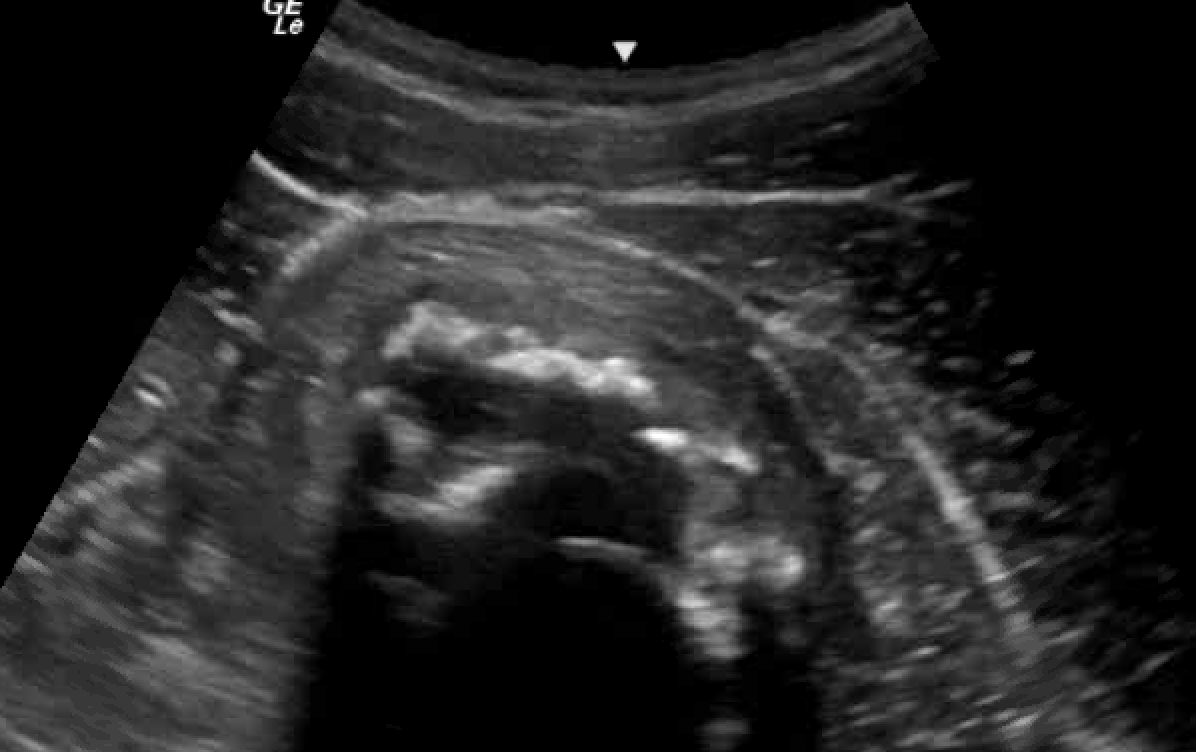

Unlabeled short axis view of the right quadriceps muscles with myositis ossificans four weeks after initial injury and two weeks after aspiration.